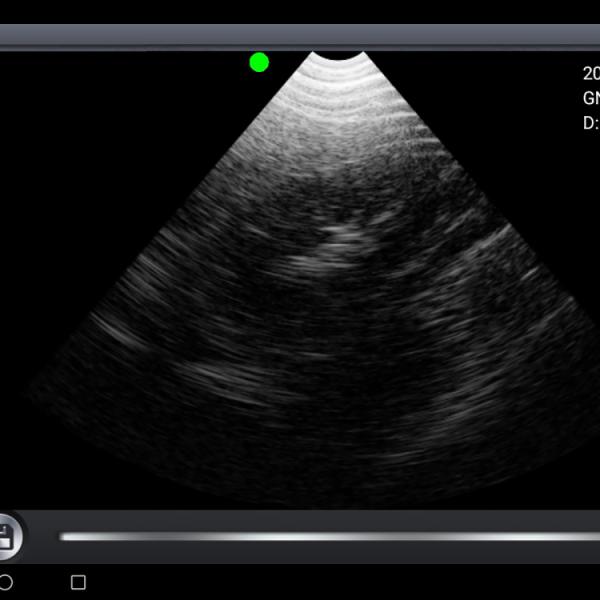

3.5 MHz 256 levels Mechanical veterinary wireless ultrasound probe

Introduction

The intelligent wireless B -ultrasonic tester uses the latest wireless data transmission technology and it is the latest generation of animal ultrasound imaging equipment. It mainly used for pregnancy testing of animals such as pigs or sheep, etc.This manual is intended to provide users with a complete introduction to intelligent B -ultrasonic tester (for mobile Android). Please read it carefully before operation. Thank you for your trust and we provide you with an animal ultrasound imaging system .

Features

3.5 MHz 256 levels Mechanical veterinary wireless ultrasound probe Images |